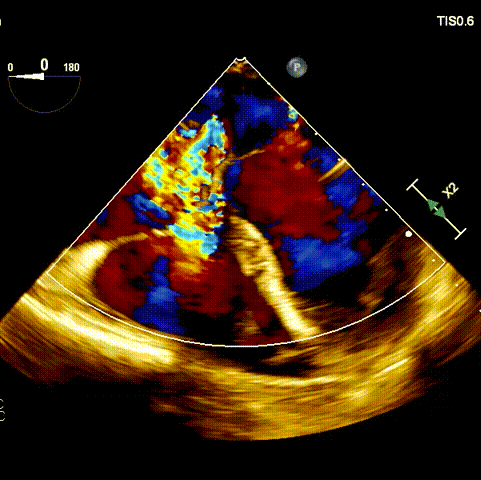

術前超聲

接受手術的為一名80歲男性,因“心悸2年,氣喘伴下肢水腫半年”入院。超聲心動提示“極重度三尖瓣反流,右房及右室明顯擴大,右心收縮功能輕度減低,左心收縮功能正常,肺動脈壓力正常”?;颊咄瑫r合并有“持續(xù)性房顫”及“慢性心力衰竭”,病史持續(xù)2年,規(guī)律口服抗凝及強心、利尿治療治療效果不佳,癥狀持續(xù)。經(jīng)廈心心臟團隊評估后,認為患者三尖瓣極重度反流并伴有心衰表現(xiàn),長期內(nèi)科藥物治療效果不佳,且患者高齡、外科手術風險高,因此決定采用微創(chuàng)經(jīng)頸靜脈LuX-Valve Plus三尖瓣置換系統(tǒng)為患者治療。